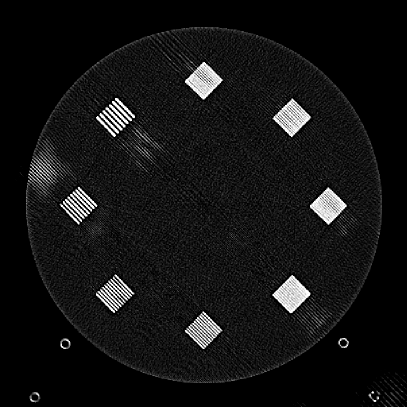

Figure 10: Clinical Standard hybrid IR vs JENG performance, with a display window center of 650 HU and a window width of 1500 HU. The spatial frequencies for bar patterns from top going clock-wise are 1.2, 1.0, 0.9, 0.8, 0.7, 0.6, 0.5, 0.4 mm-1. (a) The clinical Standard hybrid IR at L1 denoising strength using a soft tissue high contrast kernel. Note that significant aliasing streaking artifacts are present near the bar patterns. (b) JENG at a comparable L1 noise level but with much clearer bar pattern and fewer artifacts than the clinical standard hybrid IR. (c) The clinical standard hybrid IR at a stronger denoising strength of L3. (d) JENG at a comparable L3 noise level.

The first experiment we performed was a visual comparison of in-plane spatial resolution between JENG and the clinical standard hybrid IR. We used the ACR phantom module 4 for this evaluation, which has 8 resolution bars of various spatial frequencies from 0.4 mm-1 to 1.2 mm-1. To obtain a fair comparison, we matched the image noise variance in the uniform regions of JENG and the clinical standard hybrid IR and studied their in-plane spatial resolution and undersampling streaking artifacts. In addition, we performed two sets of experiments. The first set of experiments matched their image noise variance at the L1 denoising strength of the clinical standard method with a noise variance of 33926 in the uniform regions. The second set of experiments matched their image noise variance at stronger L3 denoising strength of the clinical standard method with a noise variance of 12988 in the uniform regions.

Fig. 10 is an example image for resolution bars and the spatial frequencies for the bar patterns from top going clockwise are 1.2, 1.0, 0.9, 0.8, 0.7, 0.6, 0.5 and 0.4 mm-1. Fig. 10(a) is the resolution bars reconstructed by the clinical standard hybrid IR at L1 denoising strength. Fig. 10(b) is JENG reconstructed at an image noise variance comparable to the L1 denoising. Fig. 10(c) is the clinical standard hybrid IR at a stronger L3 denoising strength and we can observe that the result at L3 denoising leads to less image noise than the result at L1 denoising in Fig. 10(a). Fig. 10(d) is JENG at an image noise variance comparable to the L3 denoising. To help readers better see the image quality difference between the clinical standard hybrid IR and JENG, Fig. 11 is the difference image between the two algorithms at L1 denoising. A noticeable difference between the clinical standard hybrid IR and JENG is that the clinical standard method in Figs. 10(a) and (c) have strong undersampling aliasing artifacts near the phantom periphery, which show a pattern of high density streakings and the streakings point along the direction of X-rays. In addition, the magnified sub-figures show that the bar pattern at 0.8 cycles/mm is unresolved with blurry details. In contrast, JENG in Figs. 10(b) and (d) effectively decimates the undersampling artifacts and the bar pattern in the magnified sub-figures of JENG is completely resolved with clearer details.

For the clinical standard hybrid IR, a possible cause for its loss of image resolution and the presence of aliasing artifacts in the image periphery can be explained by the Nyquist-Shannon sampling theorem. Nyquist-Shannon sampling theorem concludes that the discrete projection sampling rate for an application that requires Fourier Transform and data interpolation must be sufficiently high to avoid alias in the frequency domain and capture all the needed information in the continuous image domain. Given that the clinical standard hybrid IR involves Fourier Transform and data interpolation operations, the low projection sampling rate at a high helical pitch of 2.8 might lead to aliasing artifacts and a loss of spatial resolution for the clinical standard method. In contrast, JENG has no Fourier Transform or data interpolation operations and is completely based on linear algebra and acquisition physics modeling. Therefore, JENG is not limited by Shannon-Nyquist Theorem and its images are less susceptible to aliasing artifacts and show clearer bar patterns.